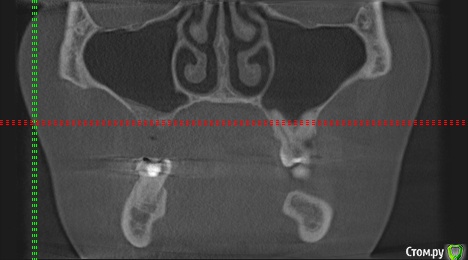

wladdX Опубликовано 27 февраля, 2019 Поделиться Опубликовано 27 февраля, 2019 (изменено) Скриншоты Сколько успел Изменено 27 февраля, 2019 пользователем wladdX Ссылка на комментарий

red_butler Опубликовано 27 февраля, 2019 Поделиться Опубликовано 27 февраля, 2019 соустье нужно посмотреть, но предварительно - не вижу препятствий для проведения открытого синуслифта Ссылка на комментарий

wladdX Опубликовано 27 февраля, 2019 Поделиться Опубликовано 27 февраля, 2019 Похоже, я загрузил скрины другого пациента (на диске записаны 2 исследования), исправляюсь. Ссылка на комментарий

kramer Опубликовано 27 февраля, 2019 Поделиться Опубликовано 27 февраля, 2019 Закрытый синус-лифт + 10 мм имплантат Ссылка на комментарий

red_butler Опубликовано 27 февраля, 2019 Поделиться Опубликовано 27 февраля, 2019 8 мм имплант и закрытый синус без графта Ссылка на комментарий

колесников Опубликовано 3 марта, 2019 Поделиться Опубликовано 3 марта, 2019 У вас речь идёт об одном импланты в области 16. Одиночный короткий Имплант не рекомендуется ни одним из производителей имплантов. Открытый синуслифтинг не показан из за особенностей строения пазухи в этой области,показан закрытый. Так же рекомендовал бы Астра тек,4.5х9. А также:дистализация 17го и имплантация в области 47.. либо удаление 17го,имплантация 17,16,47 Ссылка на комментарий